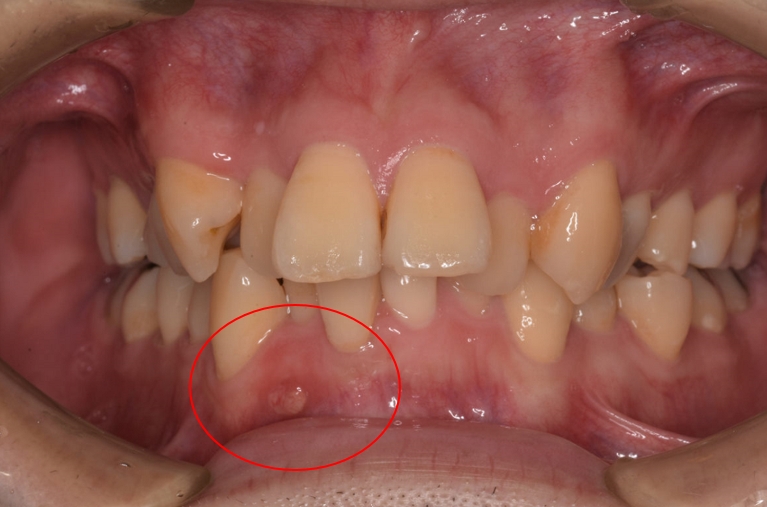

よく見ると赤で囲った部分に

ニキビのような出来物があります

ご本人は気づいていらっしゃらなかったようです